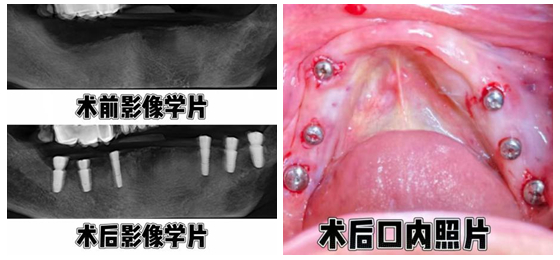

术中,向峰副主任医师采用不切开、不翻瓣、无缝合的微创种植技术,仅用1小时10分钟便为患者下颌精准植入6枚种植体。与传统种植手术相比,该技术创伤小、出血少、疼痛轻,无需切开牙龈和术后缝合,大大缩短了手术时间,降低了术后感染风险。手术全程患者生命体征平稳,无任何不适感。